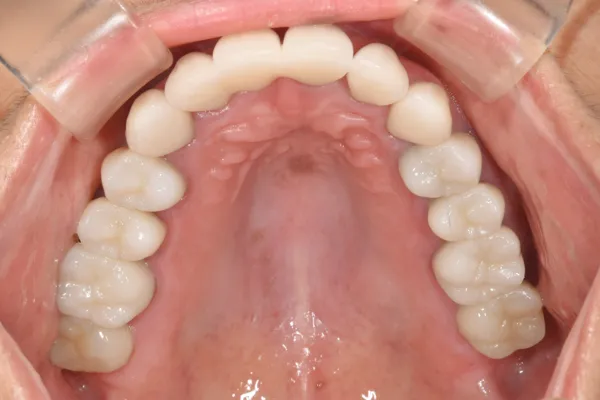

主訴 全体の審美性を高めたい

治療方法 全顎をオールセラミック補綴で治療

治療期間 約2年

通院回数等 40回

費用 4,004,000円(税込)

リスク・副作用 色調を合わせるのが難しい